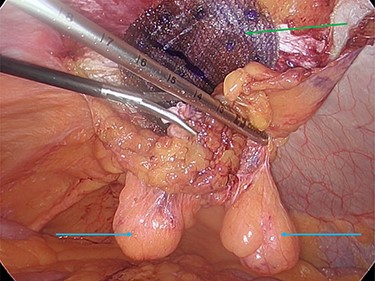

Intraoperatively, we noticed omentum incarcerated in the hernia sac (Fig. 2).

Laparoscopic view of the incarcerated omentum in the umbilical hernia (green arrow).